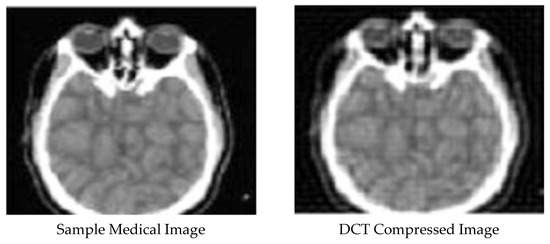

Enhanced and Compressed Output

5. Discussion

| 1 | DCT compressed Image | 0.976102286 | 4.15 × 10−5 | 89.97979612 |